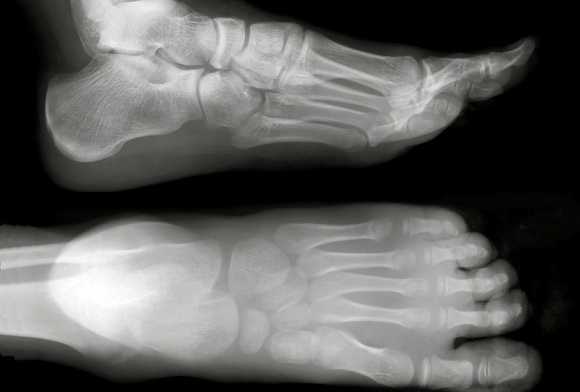

Рентген стопы в двух проекциях

Рентген стопы в двух проекциях чаще всего назначается для диагностики переломов, а также деформирующих патологий, таких как артрит или артроз. Также этот метод исследования дает возможность оценить изменения в суставе большого пальца при подагре.

- Для съёмки в прямой проекции пациент ложится на стол рентгеновского аппарата, вытягивает ноги вперёд. Делается снимок одновременно двух стоп, даже если тревожные симптомы отмечаются только в одной.

- Для съёмки в боковой проекции пациенту необходимо перевернуться на бок. Рентгенолог располагает трубку рентген-аппарата так, чтобы лучи проходили перпендикулярно к боковой поверхности стопы.

Для выявления плоскостопия обычно выполняют рентген ступней с нагрузкой в боковой проекции. Для этого ступня ставится на подставку внутренней стороной к рентгеновской кассете. Другая нога отводится в сторону. При такой укладке на снимках отмечают три черты:

- I - проходит от первого пальца к пяточной кости;

- II - проходит от точки соединения пяточной кости с первой чертой до ладьевидно-клиновидного сочленения;

- III - проходит от этого же сочленения к первой плюсневой кости.

Соотнося эти линии, измеряют высоту и угол их пересечения. Высота - это перпендикуляр, опущенный из точки соединения второй и третьей черт вниз, на первую горизонтальную. В норме высота должна быть больше 35 мм, а угол - от 125 до 130°.

Отклонение от указанных норм говорит о наличии плоскостопия. Для выявления степени патологии нужно оценить, насколько фактические параметры стопы отличаются от нормальных:

- I степень. Высота свода равна 25-35 мм, угол - 131-140°. При такой патологии пациента беспокоит усталость в ногах при физической нагрузке.

- II степень. Высота свода равна 17-24 мм, угол - 141-155°. В этом случае пациент чувствует усиление боли при длительной ходьбе и физических усилиях.

- III степень. Высота - меньше 17 мм, угол - больше 155°. При такой патологии пациент постоянно чувствует боли в голенях, пояснице и ступнях.